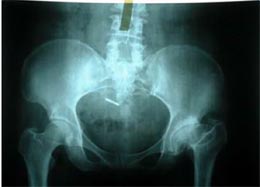

病例三

患者女性,45岁,左髋关节先天性脱位,股骨头坏死,疼痛明显,活动受限。采用生物固定全髋关节置换术,

髋臼予以加深没有植骨。术后5年复查,假体没有松动,关节功能良好,没有疼痛。